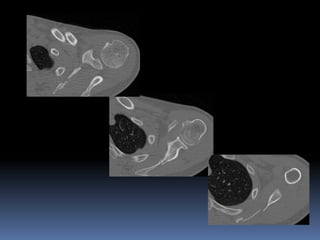

 Suspected scapula fracture

3D CT is done to assess

scapula and adjacent

injuries.